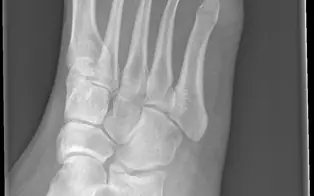

Entorse de Chopart